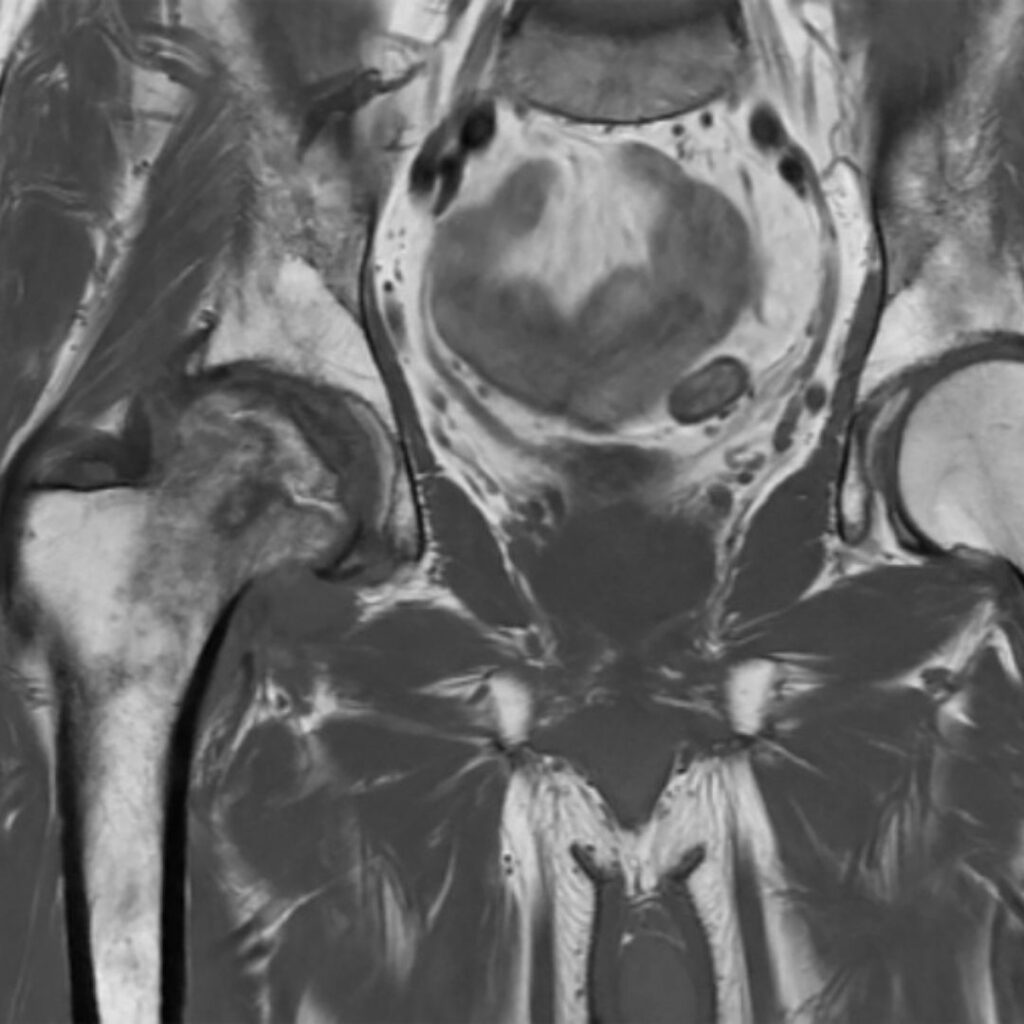

Successivamente, le indagini radiologiche diventano fondamentali per valutare l’entità del danno e stabilire come intervenire. Le radiografie iniziali possono evidenziare alterazioni di densità e disomogeneità nella trama ossea, mostrando progressivamente eventuali deformità della testa femorale. Tuttavia, la risonanza magnetica rimane il metodo più accurato, che permette di identificare la patologia anche nelle fasi precoci, quantificare l’area osteonecrotica, individuare la sede esatta della lesione e distinguere con precisione la componente ossea da quella cartilaginea.

Infine, la TAC può integrare la diagnosi, evidenziando zone di osteosclerosi circostanti o fratture dell’osso subcondrale.